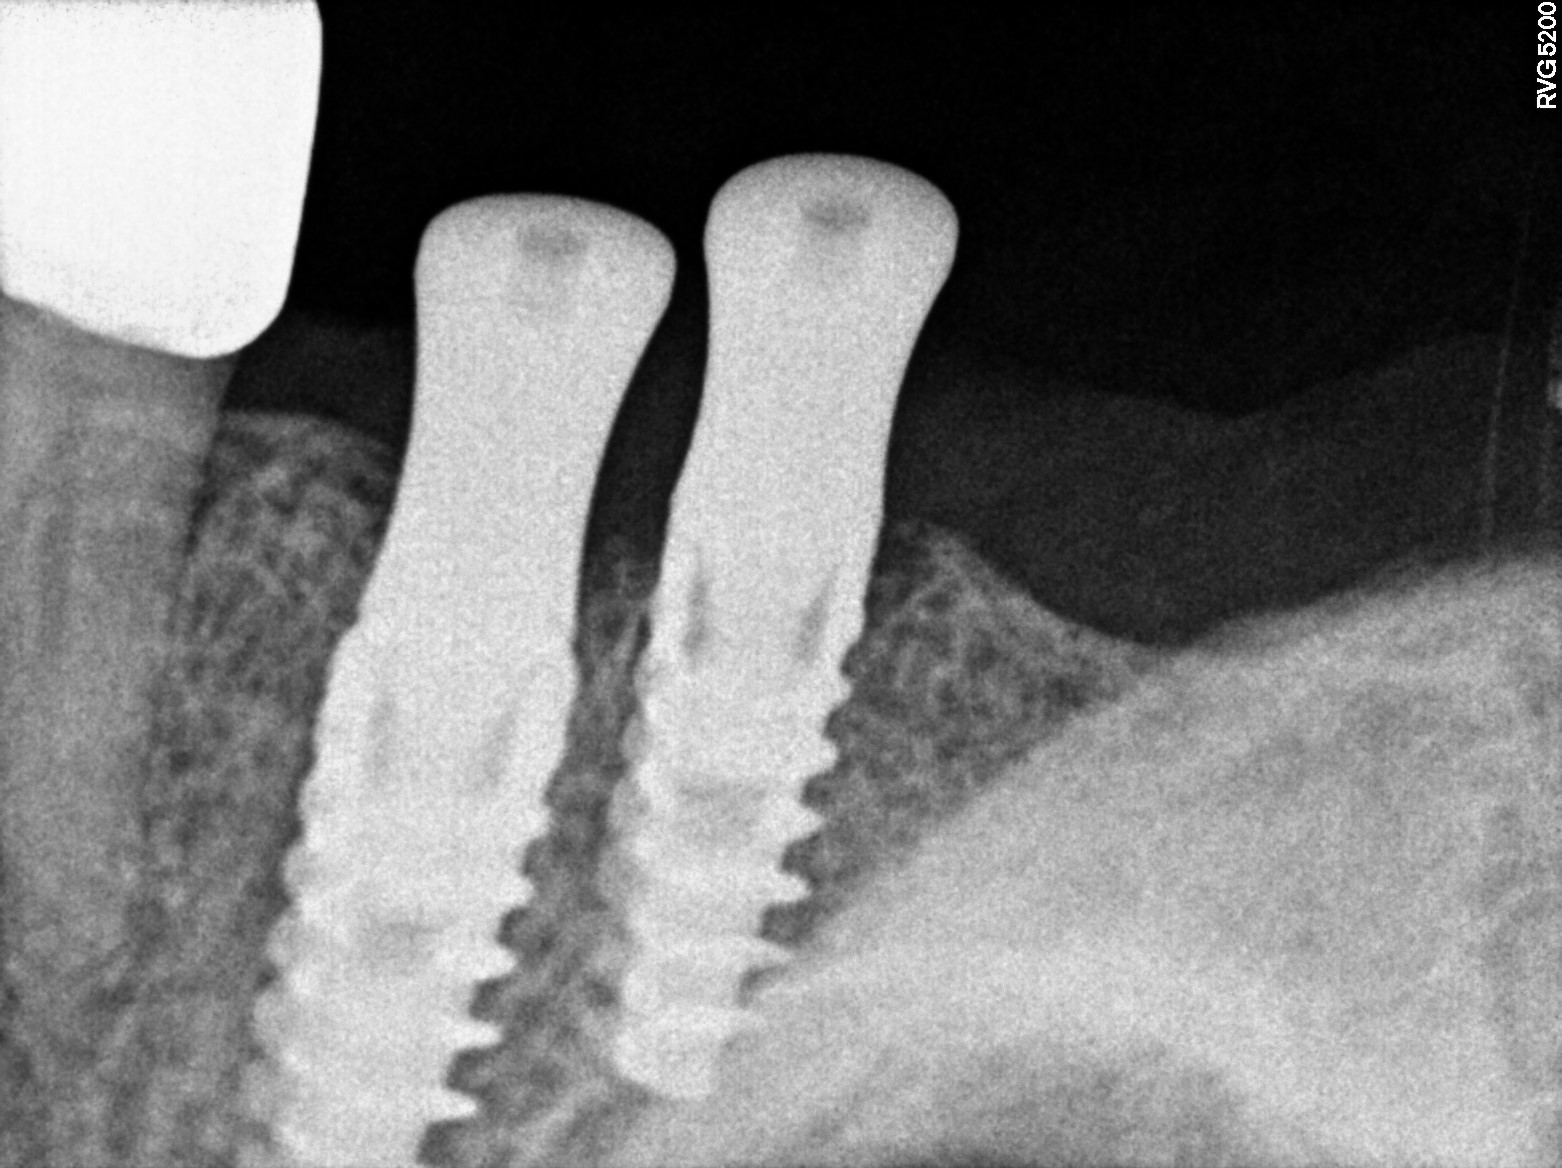

Dental Radiographs FHIR: DocumentReference · LOINC 24641-7

R71.jpg

24641-7